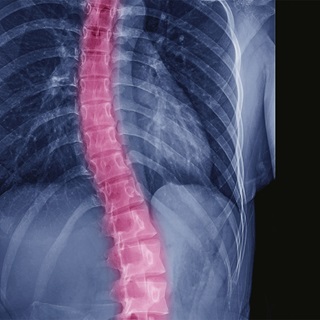

Scoliosis is a curvature of the spine that occurs most often in adolescents, but adults develop the condition too. An estimated 60 percent of the older population have what is known as adult scoliosis. As people live longer and are more active, this number is expected to increase.

Adult scoliosis is most common in people between the ages of 50 and 80. It is characterized by a side-to-side curvature of the spine caused by degeneration of the spine's facet joints, which act as hinges to help the spine bend.

Spinal curvature is measured in degrees. Unlike the slow progression of adolescent scoliosis, adult scoliosis can remain the same, can progress slowly and can progress at higher rates of more than 3 degrees a year. Often, the condition causes significant physical pain and can impact quality of life.

Standing X-rays, from the front and side, will be taken to document the curvature of your spine and to determine how fast the curve is progressing.